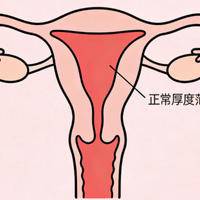

在试管婴儿的整个流程中,子宫内膜的厚度是受关注的一个指标。很多姐妹在移植前做B超时,都会紧张地盯着报告单上那个内膜厚度的数字,然后忍不住去网上查:我这个厚度到底正不正常?为了解答这些困惑,临床上确实有一个大致的试管内膜厚度正常对照表,但它不是死板的及格线,而是一个需要结合月经周期、用药方案和个人情况来综合看待的范围。本文就把这个对照表给大家讲清楚,同时聊聊厚度之外的几个关键细节。试管内膜厚度正常对